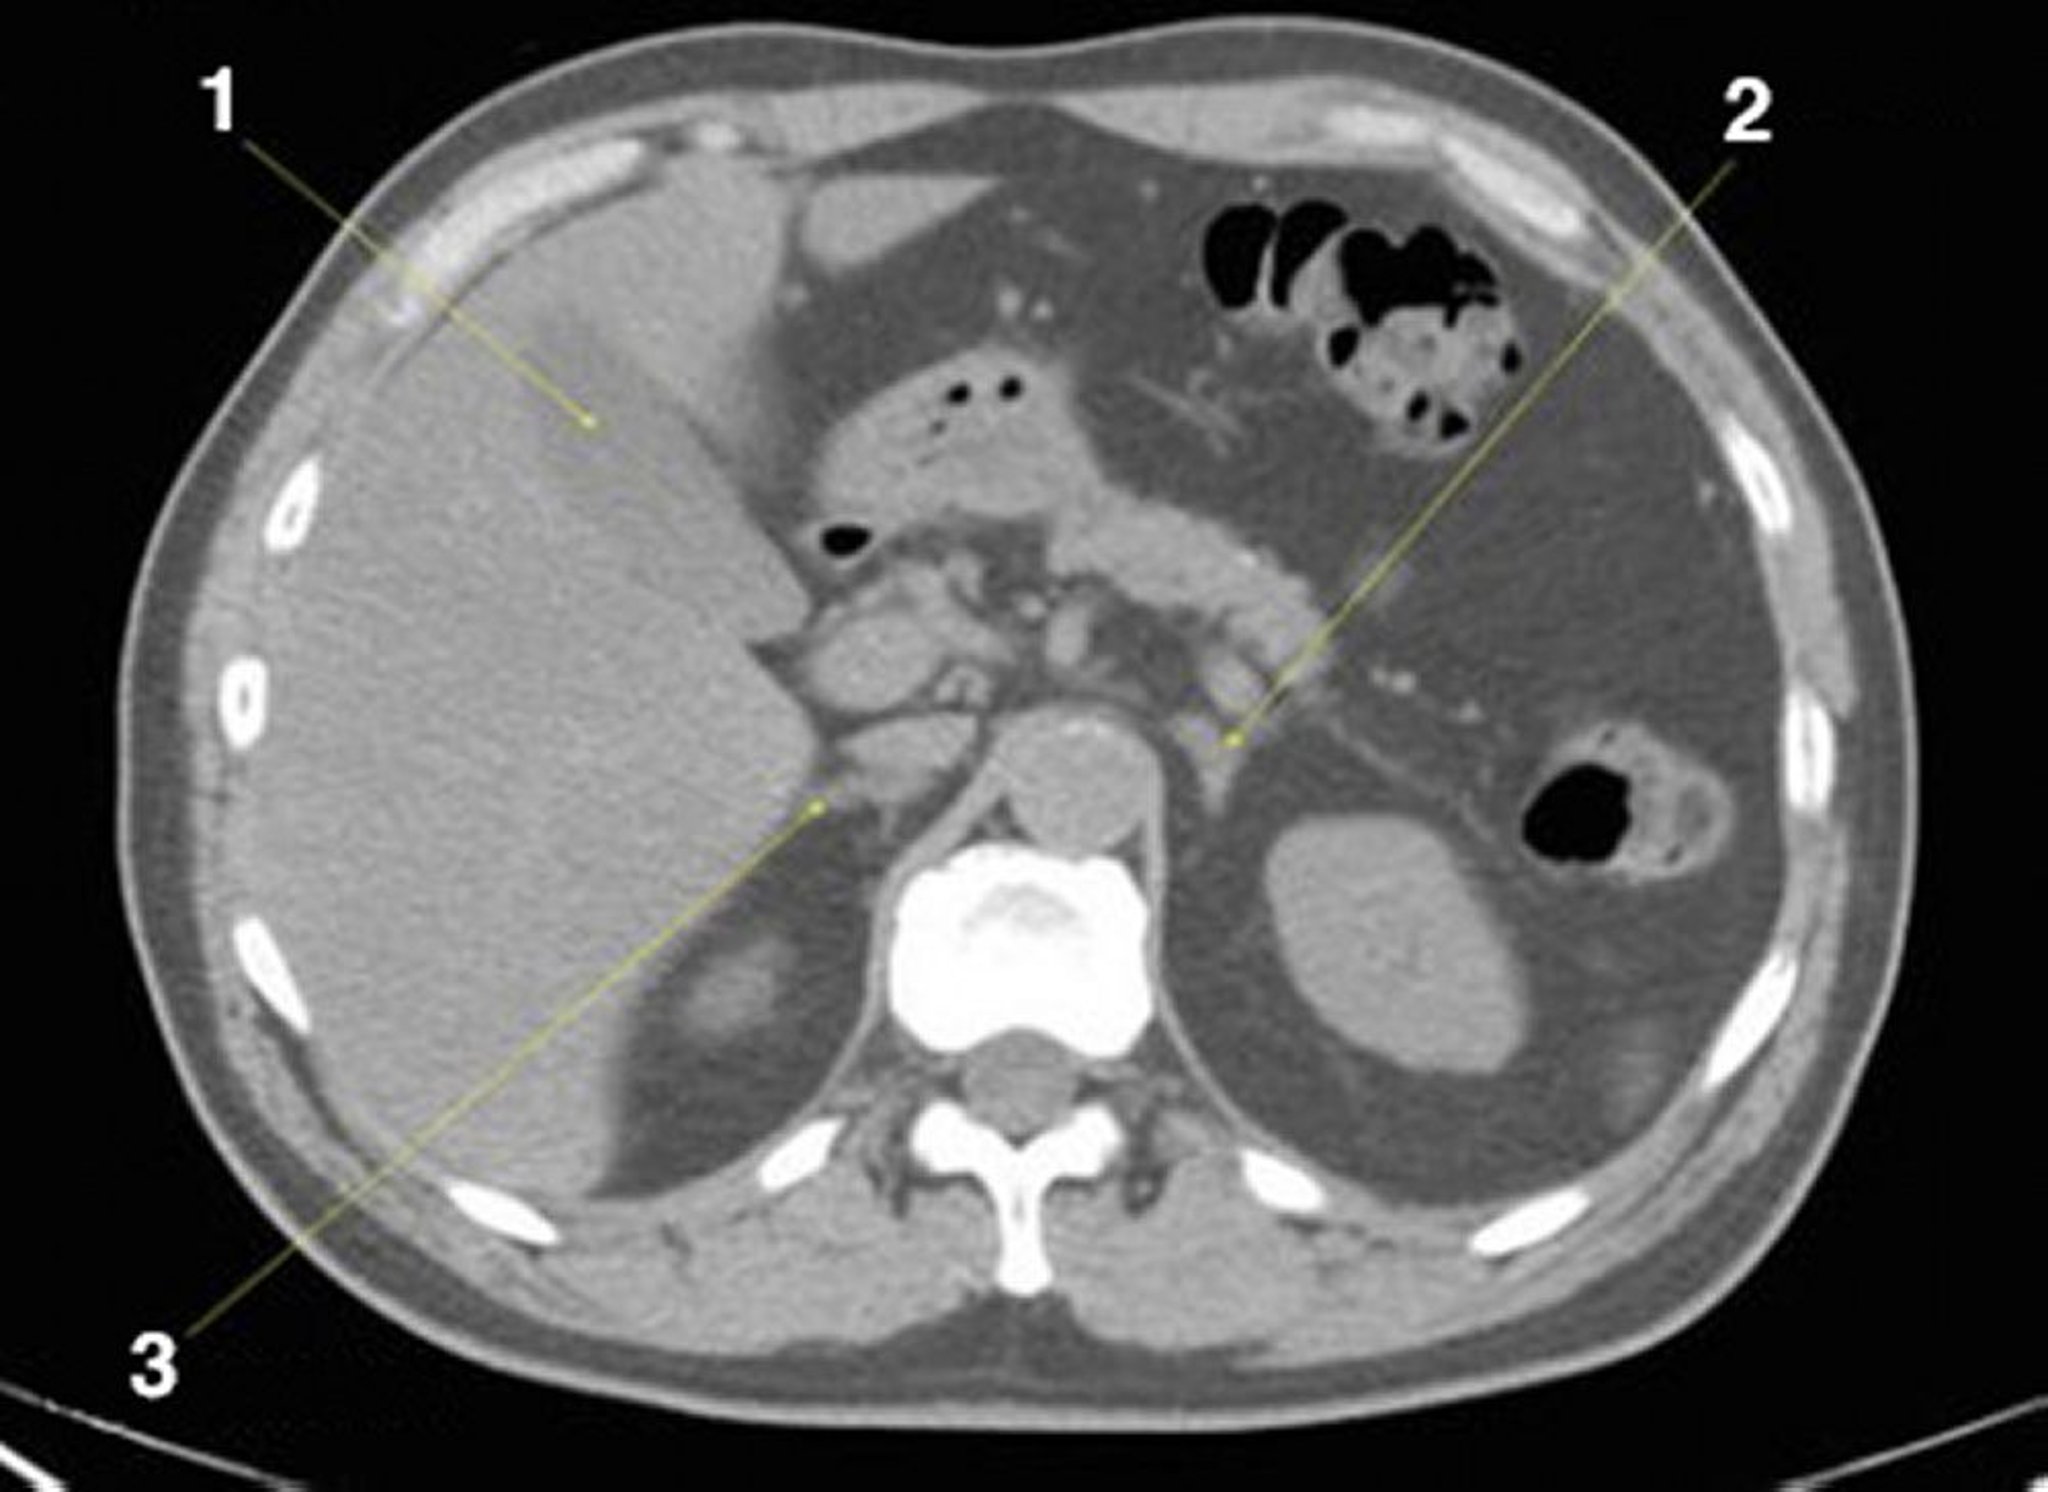

CT-Scan von Abdomen und Becken mit normaler Anatomie ohne Kontrastmittel (Folie 8)

1 = Gallenblase; 2 = linke Nebenniere; 3 = rechte Nebenniere.